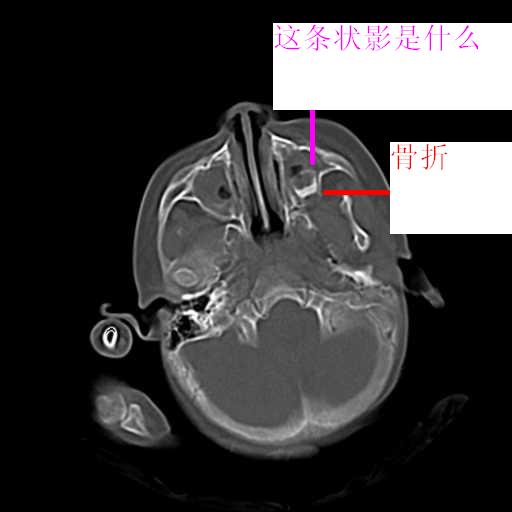

m,3y,外伤一天,无明显其它症状.

右侧颅底后可疑颅窝骨折.

双侧双颌窦及筛窦内可见密度增高影,考虑付鼻窦炎,上颌窦后壁骨折.